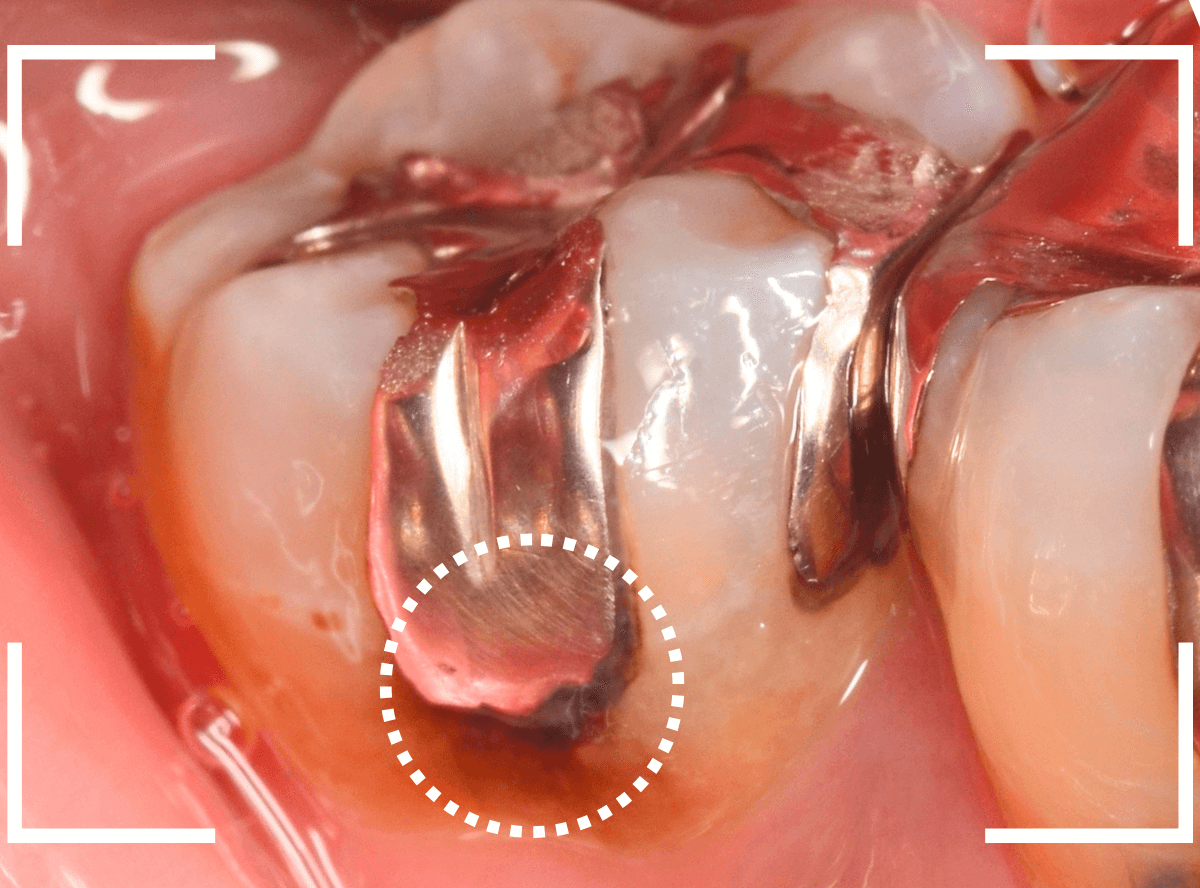

「つめものが外れて、噛むと痛い」という訴えで来院された患者さんさんです。

一見で、表面が虫歯になっているのと、レジンが劣化しているのがわかります。

レントゲン写真で確認します。

〇部が当該の歯です。

症状もあるので、虫歯が深そうですが、全体がもやっとして、どこからどこまで虫歯なのかはっきりわかりません。

レジンを外し、虫歯の処置を進めます。

慎重に虫歯を除去し、一安心か、という寸前で(〇部、小さく出血しているところ)露髄してきました。

神経を除去しないとダメかもしれません。。。

神経を保護するお薬をつめて、経過観察します。

痛みが出ませんように。。。